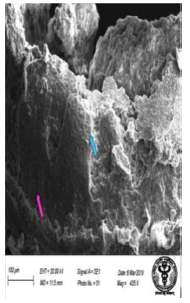

Scanning Electron Microscopic Changes

The scanning electron microscopic examination of duodenum in control rat revealed goblet cells distended with mucus in between the enterocytes (Figure 25). The epithelial cells with long and short microvilli were present (Figure 26). The rats treated with 600 mg NaF/kg b.w./day for 40 days, revealed apparent erosions and fissures at the tips of duodenal villi surrounded by enterocytes (Figure 27). There were extravasation of red blood cells observed at specific sites of villous surface (Figure 28). On the surfaces of the crypt orifices, villi appeared to be lacking. The fluorotic rats have wider crypt mouths and corrugations in their duodenum. (Figure 29,30). The villus had deep irregular corrugations. The goblet cell orifices were also visible in the duodenum of fluoridated rats (Figure 31). Significant damage characterized by erosions on the mucosal surface and leaf-like villi showed signs of autolysis. Presence of bleb was observed in the duodenal mucosa of fluoridated rats indicating injury (Figure 32).

Figure 27: Scanning electron micrograph of duodenum of rat treated with 600 mg sodium fluoride showing erosions (↑) and fissures (↑). X 1000.

Figure 28: Scanning electron micrograph of duodenum of rat treated with 600 mg sodium fluoride showing extravasion of erythrocyte (↑). X 453.

Figure 29: Scanning electron micrograph of duodenum of rat treated with 600 mg/kg b.w /day of NaF for 40 days and showing absence of villi and wide crypt mouths (↑). X 746.

Figure 30: Scanning electron micrograph of duodenum of rat treated with leaf extract of 600 mg/kg b.w./day of NaF for 40 days showing mucosa and corrugations (↑). X 524.